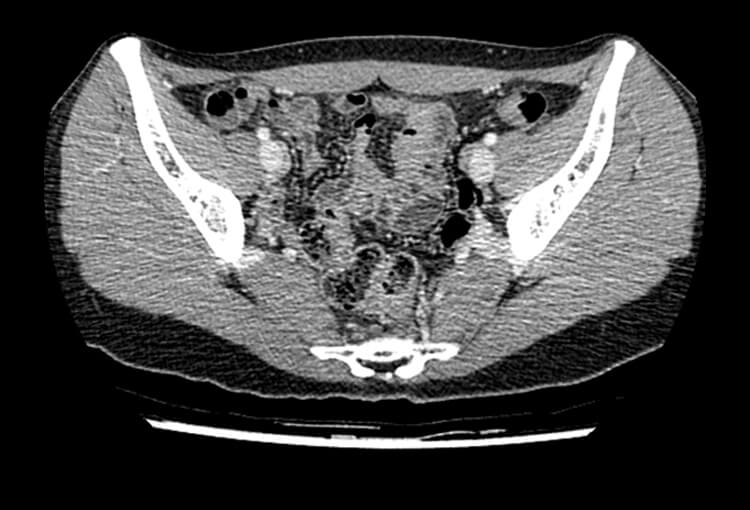

Before and After Denoising

120 kV / 20 mAs / 1 mm

Before FBP (Noise 189) VS After ClariCT.AI (Noise 46) 76% Denoising